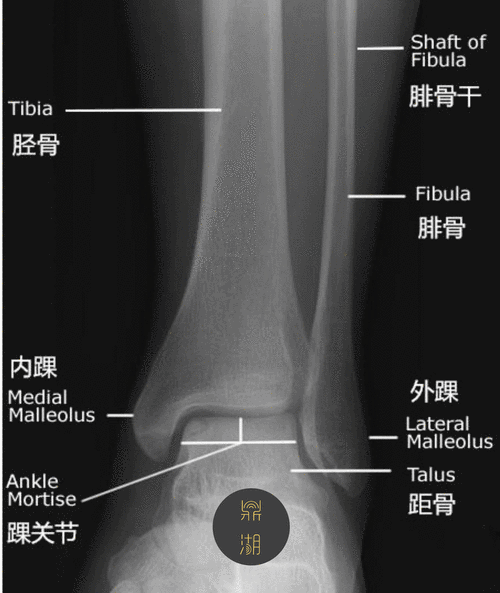

x线解剖 | 踝关节解剖

详细的踝关节x线解剖变异解读测量